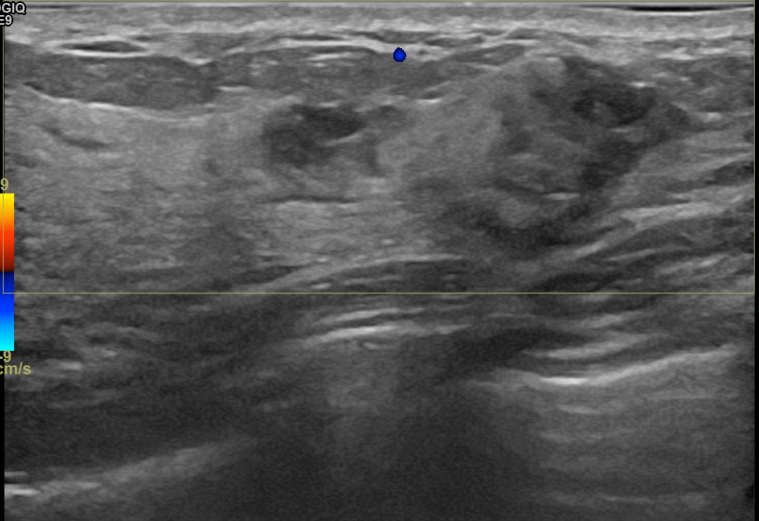

상기환자는 만져지는 멍울로 내원하신 30대후반

여성분으로 의심스러운 우측혹 조직검사 시행해 침윤성암으로 진단되었습니다